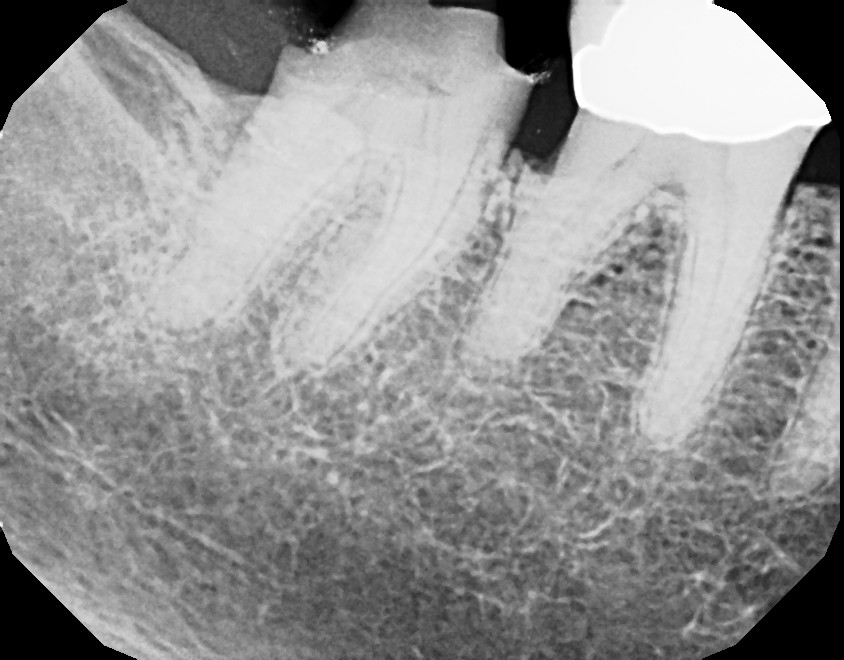

Below are pictures of a recent case of mine. This 10+ year old crown that developed decay (cavity) around the margin where tooth meets crown. Always pay attention to sensitivity around fillings and crowns and advise your dentist when symptoms develop, so you can stay away from roots canals. In this particular case, root canal was required because the decay reached too close to the nerve.